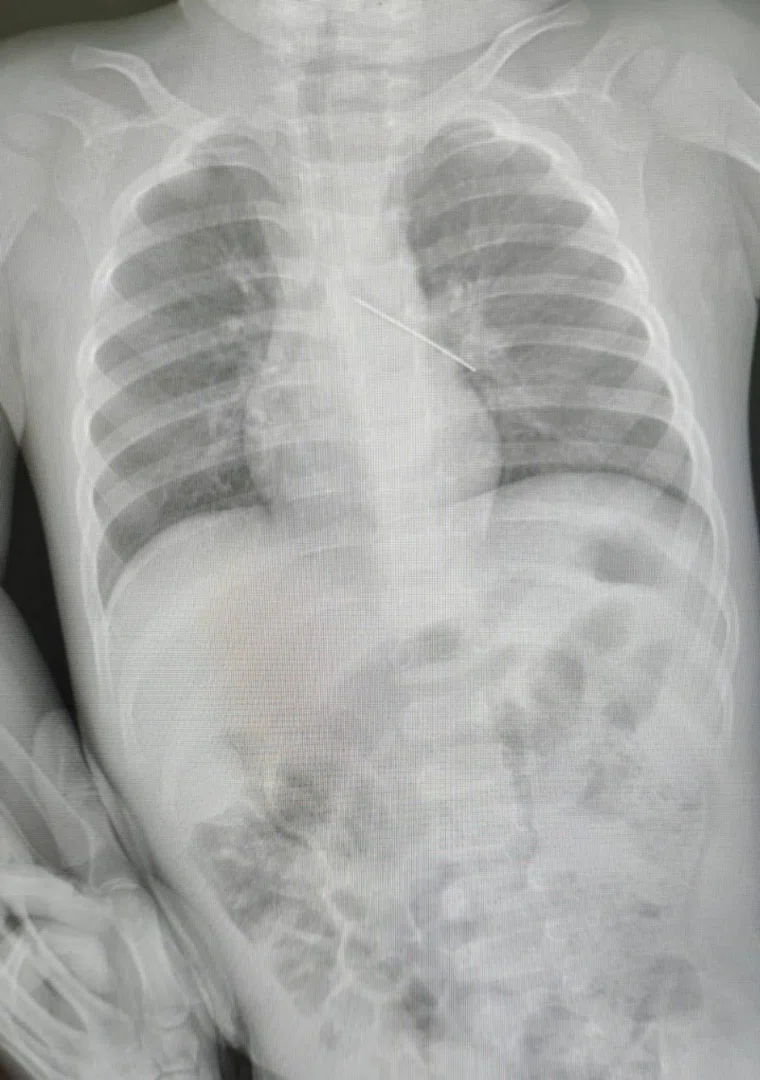

В ХМАО младенец проглотил булавку. Фото

Булавка застряла в бронхах малыша

В Сургуте (ХМАО) малыш в возрасте 1 год и 5 месяцев экстренно поступил в больницу. Как оказалось он проглотил булавку, которая застряла в бронхах. Подробности спасения малыша сообщила глава Центра охраны материнства и детства Лариса Белоцерковцева.

«К нам экстренно поступил малыш (1 год и 5 месяцев), который проглотил английскую булавку. Мама вовремя заметила беду и незамедлительно доставила ребенка в больницу. После проведенного обследования выяснилось, что булавка оказалась в бронхах — крайне опасное положение», — сообщила главврач медучреждения в своем telegram-канале.

Врачи смогли извлечь булавку эндоскопическим способом. В противном случае ребенку пришлось бы делать масштабную операцию — торакальную.